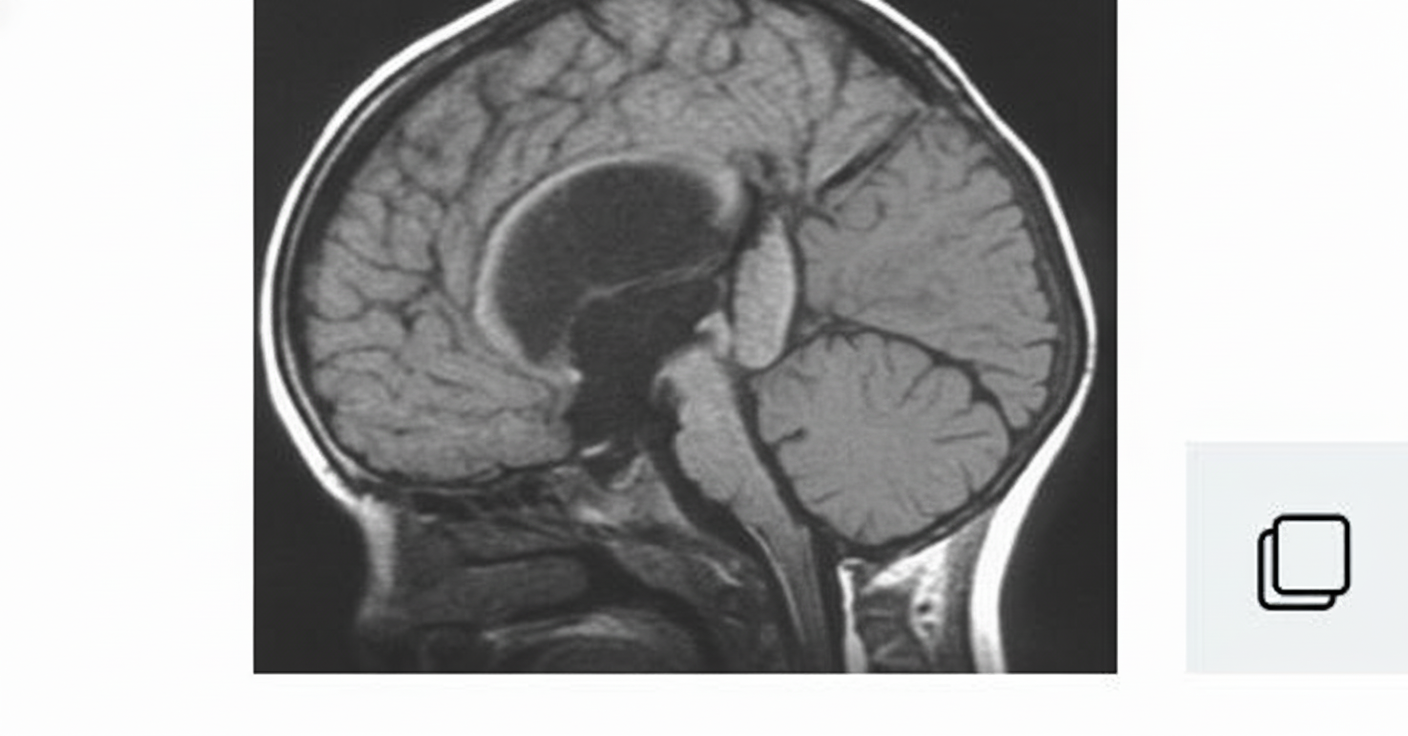

What is your diagnosis in this infant who was found to have hydrocephalus?

Explanation: ***Dandy-Walker malformation*** - Characterized by **posterior fossa cyst**, **cerebellar vermis hypoplasia**, and **elevated tentorium** with associated hydrocephalus in infants. - Classic triad includes **cystic dilatation of fourth ventricle**, **absent or hypoplastic cerebellar vermis**, and **enlarged posterior fossa**. *Chiari malformation* - Features **cerebellar tonsillar herniation** through the foramen magnum, not posterior fossa cystic changes. - Type I typically presents in adolescents/adults with **headaches** and **syringomyelia**, while Type II involves **myelomeningocele**. *Vein of Galen malformation* - Presents as **arteriovenous malformation** in the **quadrigeminal cistern** with high-flow vascular lesion. - Causes hydrocephalus due to **mass effect** and **venous obstruction**, but lacks cerebellar vermis abnormalities. *Holoprosencephaly* - Involves **failure of forebrain division** resulting in **absent or incomplete interhemispheric fissure**. - Associated with **facial dysmorphism** and **monoventricle formation**, not posterior fossa abnormalities.

Explanation: **Explanation:** **Dandy-Walker Malformation (DWM)** is a congenital posterior fossa anomaly characterized by a specific triad: hypoplasia/agenesis of the cerebellar vermis, cystic dilatation of the fourth ventricle, and an enlarged posterior fossa with upward displacement of the tentorium and torcula. **Why Microcephaly is the correct (False) option:** In DWM, the massive cystic expansion of the fourth ventricle and the resulting obstructive hydrocephalus typically lead to **macrocephaly** (enlarged head circumference) and bulging fontanelles in infants. Microcephaly is not a feature of DWM; rather, it is associated with conditions like TORCH infections or Zika virus. **Analysis of other options:** * **Hypoplasia of the vermis:** This is the hallmark anatomical defect. The vermis is often rotated superiorly and is incomplete. * **Hydrocephalus:** Occurs in approximately 70-90% of patients due to atresia of the Foramina of Luschka and Magendie or associated aqueductal stenosis. * **Ataxia:** Since the cerebellum (responsible for coordination) is malformed, patients commonly present with developmental delay, hypotonia, and cerebellar ataxia. **NEET-PG High-Yield Pearls:** * **Classic Triad:** 1. Vermian hypoplasia, 2. Cystic 4th ventricle, 3. Enlarged posterior fossa. * **Torcular-Herophili sign:** The confluence of sinuses (torcula) is displaced upwards (above the level of the lambdoid suture) due to the large cyst. * **Associated Anomalies:** Agenesis of the corpus callosum is the most common associated CNS finding. * **Differential Diagnosis:** Mega Cisterna Magna (normal vermis and 4th ventricle) and Arachnoid Cyst (mass effect on a normal cerebellum).